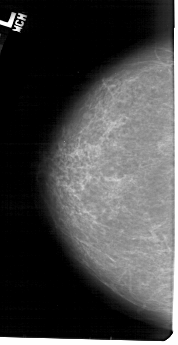

A_1418_1.LEFT_CC

LEFT_CC LINES 5161 PIXELS_PER_LINE 2656 BITS_PER_PIXEL 12 RESOLUTION 43.5 NON_OVERLAY